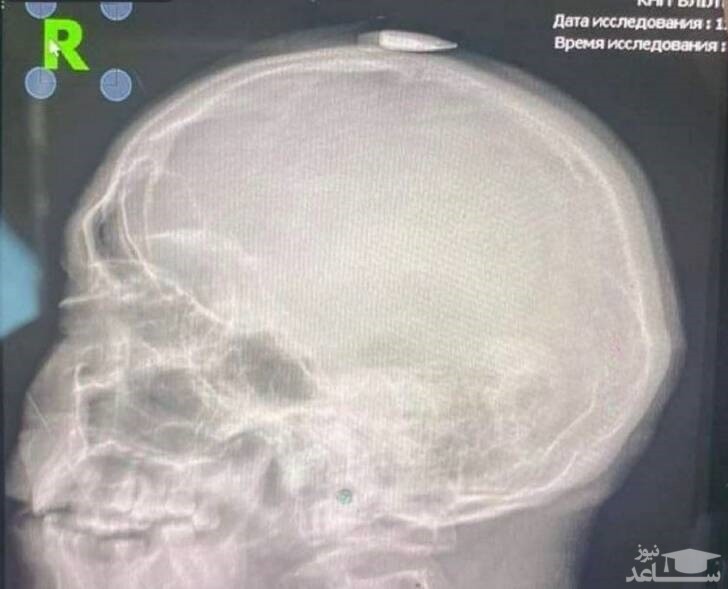

(عکس) سرباز خوششانس اوکراینی

ساعدنیوز: خوش شانسی سرباز ارتش اوکراین که از مرگ نجات یافت را در ساعدنیوز مشاهده میفرمائید.